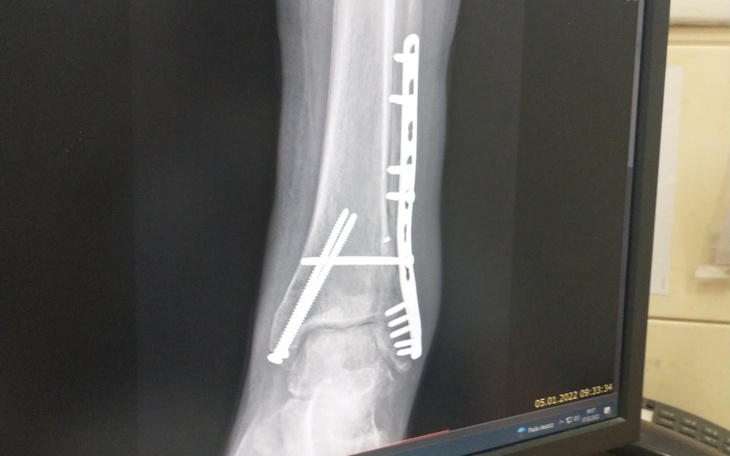

Niedawno zdarzył mi się przykry wypadek, który skończył się skomplikowaną operacją nogi w kostce. Została mi wstawiona (dożywotnio) płytka stabilizująca/łącząca stopę z piszczelem.